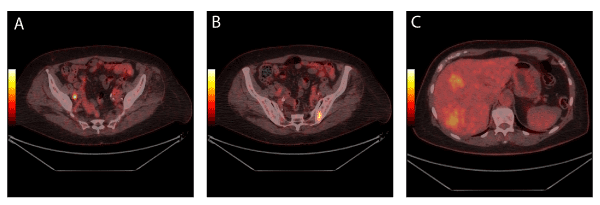

| Figure 3: Muscle invasive bladder cancer in a 73-year-old patient. The tumour could not be seen in the urinary bladder on 18F-FDG PET/CT. However, metastases were demonstrated in one lymph node in the right side of the pelvis (3A), in the bone (3B), and (3C) in the liver. |